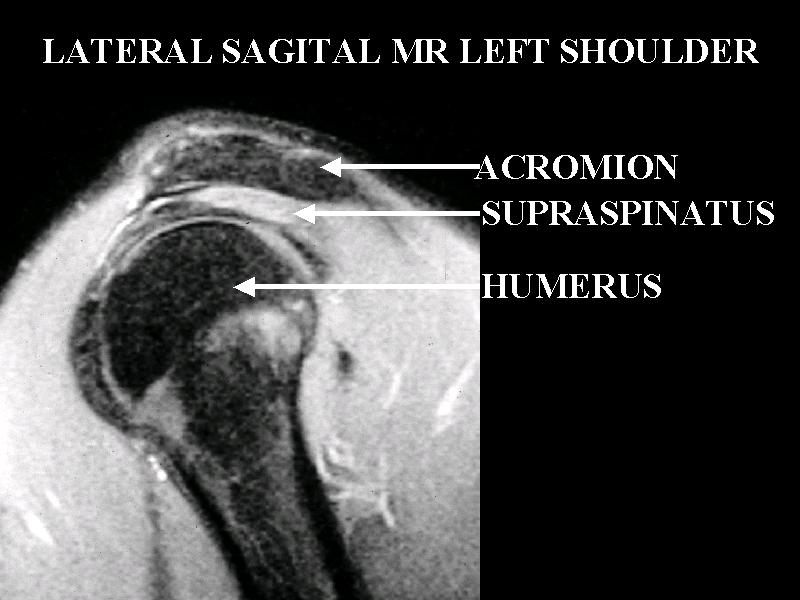

MS 196 SAG MR 2